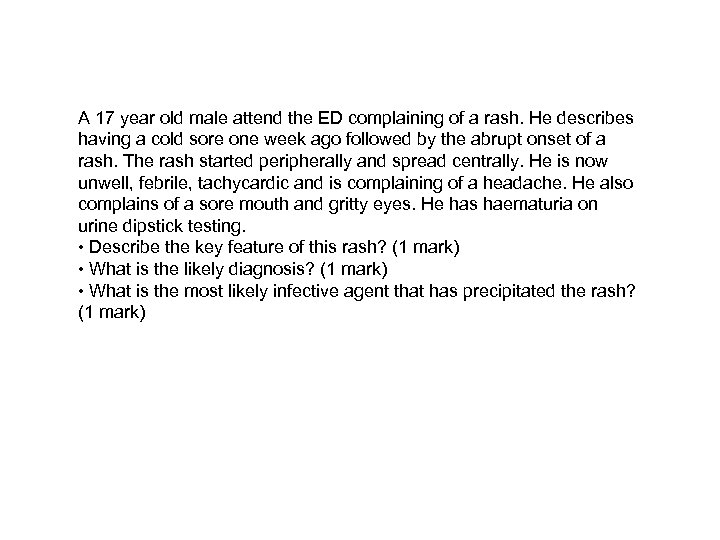

A 17 year old male attend the ED complaining of a rash. He describes having a cold sore one week ago followed by the abrupt onset of a rash. The rash started peripherally and spread centrally. He is now unwell, febrile, tachycardic and is complaining of a headache. He also complains of a sore mouth and gritty eyes. He has haematuria on urine dipstick testing. • Describe the key feature of this rash? (1 mark) • What is the likely diagnosis? (1 mark) • What is the most likely infective agent that has precipitated the rash? (1 mark)